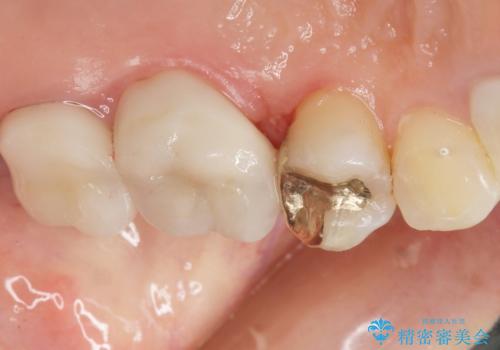

治療後はしみなくなり、違和感のない自然な咬み心地にご満足頂けました。

「割れる心配のないゴールドにしたいけれど、目立ってしまうかしら...」と心配されており、不要に歯質を削合しないよう注意を払い最小限の大きさのインレーを装着したところ、「あまり目立たなくて良かった!」とおっしゃって下さいました。

PGAとはプラチナ(白金)とゴールド(金)が主体のプラチナ金合金です。

硬さが天然歯に近いため周囲の歯への影響も少なく、さらに適合もよいため虫歯の再発リスクも軽減できます。

金属なので強度が高く、咬合力の強い方や力が強くかかる部位に適しています。

審美面でセラミックに劣りますが、奥歯の治療には最適な材料です。